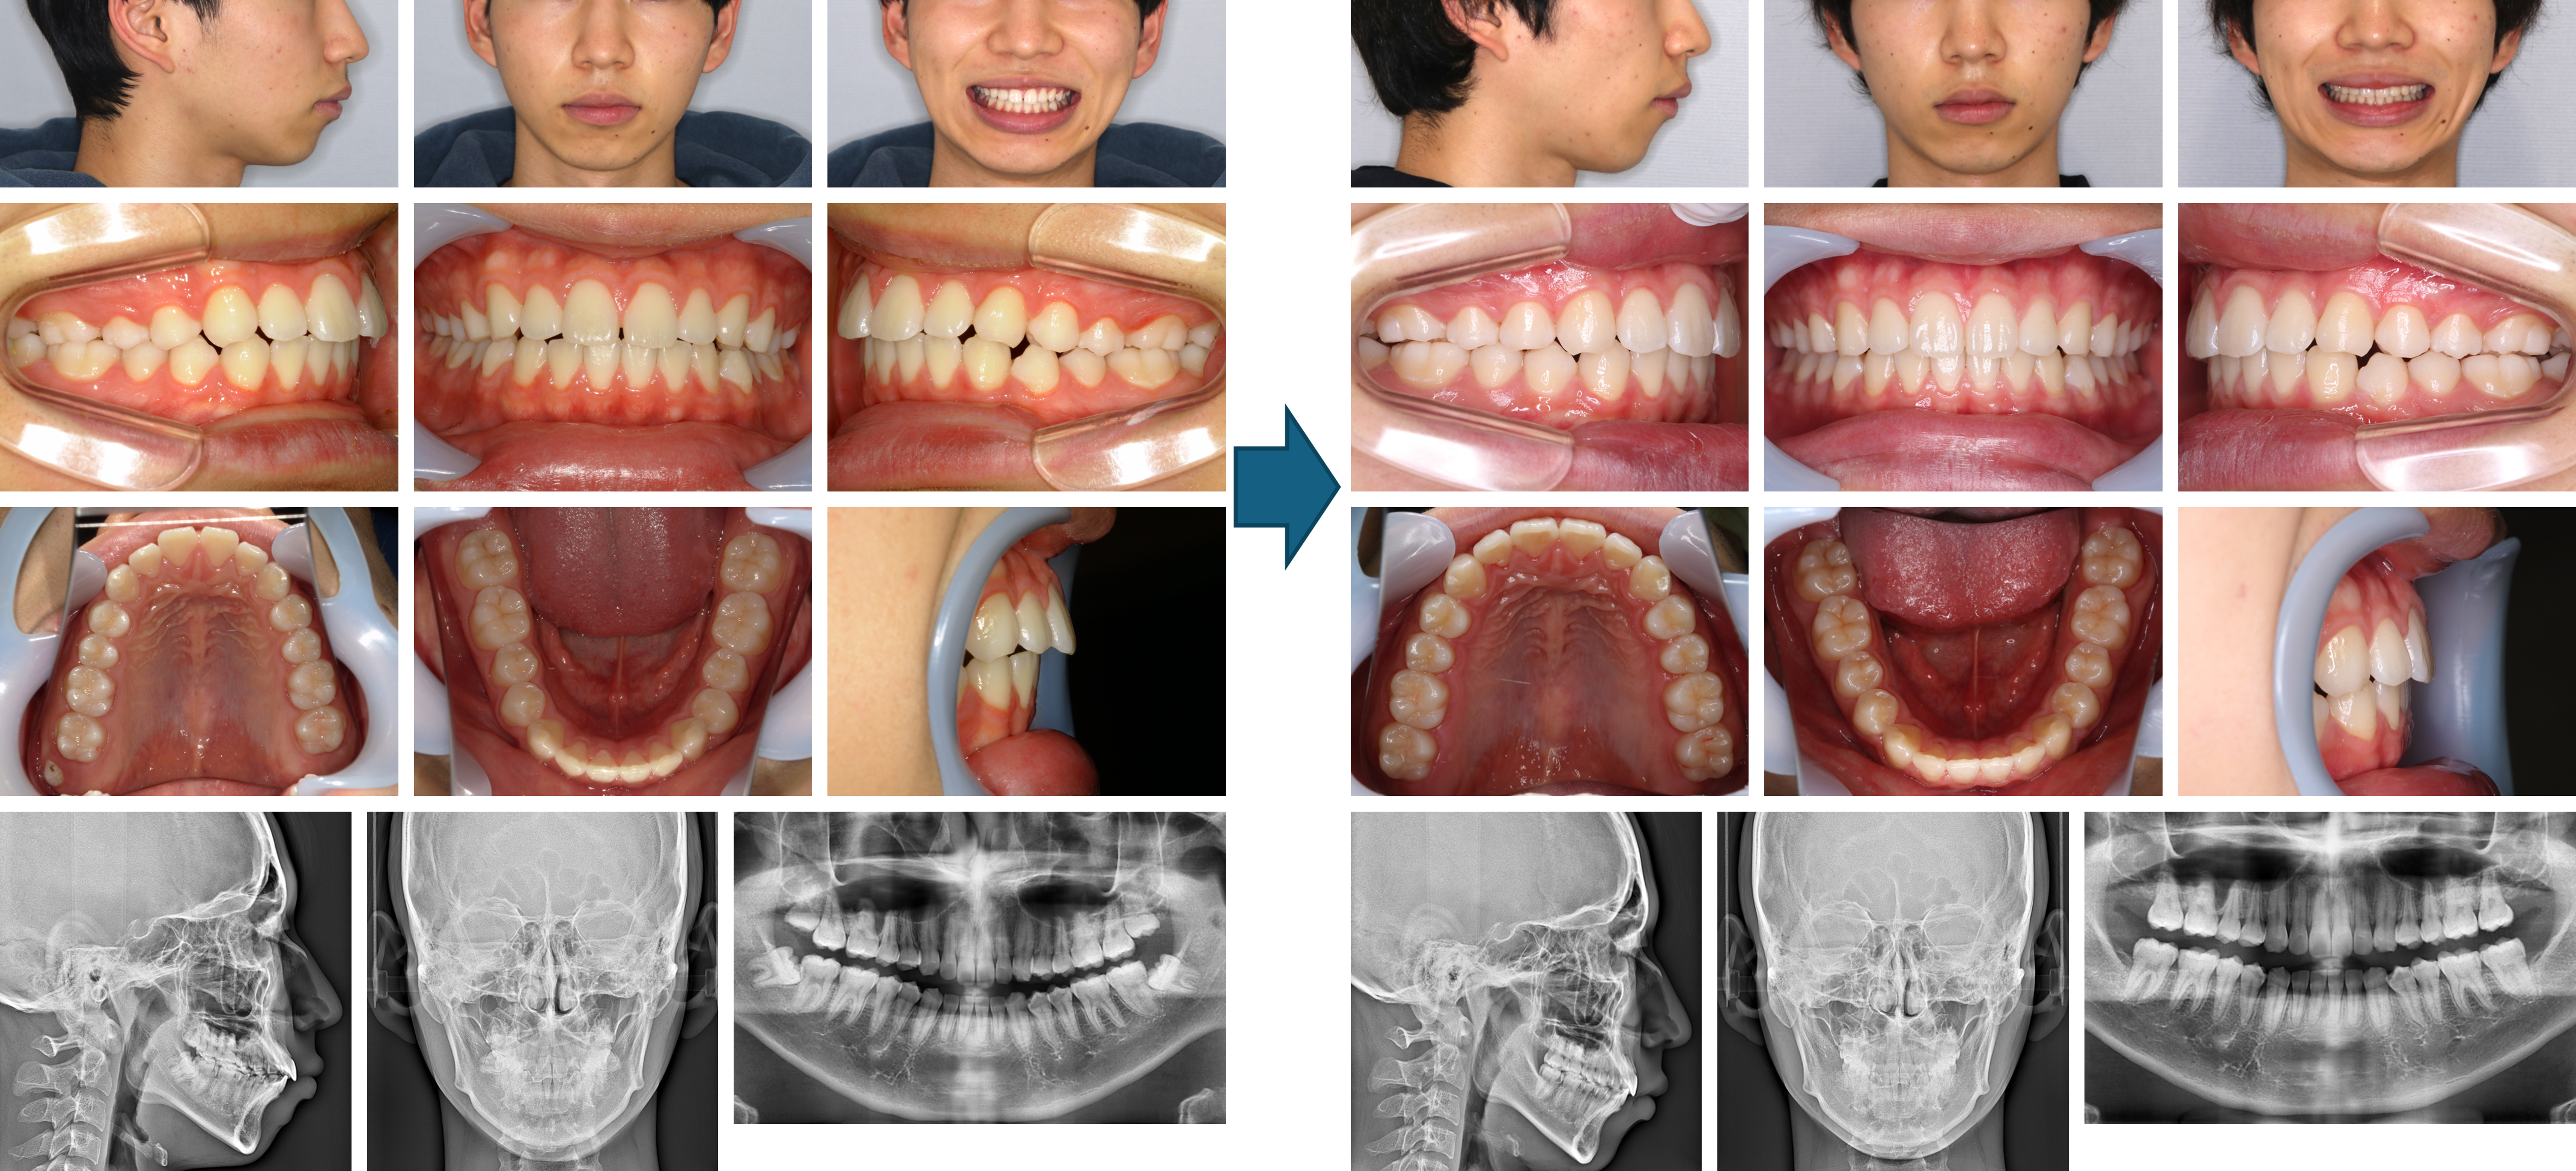

【治療例 K8255】初診時年齢:20歳2か月 / 性別:女性 / 主訴:前歯が出っ張って乱杭になっている

本症例は上顎前歯の叢生と上顎前突を主訴に来院された。下顎両側側切歯の先天性欠如を認めたほか、上顎は第三大臼歯まで萌出しており、口唇閉鎖不全が認められた。上顎両側第一小臼歯を抜歯しアライナー型(マウスピース型)矯正装置(インビザライン®)で治療した症例である。その結果口唇閉鎖も容易になり顔貌も改善した症例である。

主訴:前歯が出っ張って乱杭になっている

診断名:下顎両側側切歯の先天性欠如を認める上顎前突抜歯症例

使用した主な装置:アライナー型(マウスピース型)矯正装置(インビザライン®)、IPR

抜歯/非抜歯および抜歯部位:上顎両側第一小臼歯

※こちらの症例は2023年1月から2025年10月に行った矯正治療です(現在も経過観察中)

治療期間:2年10か月

治療回数:21回

アライナー枚数:初回40枚+追加①30枚 合計70枚使用